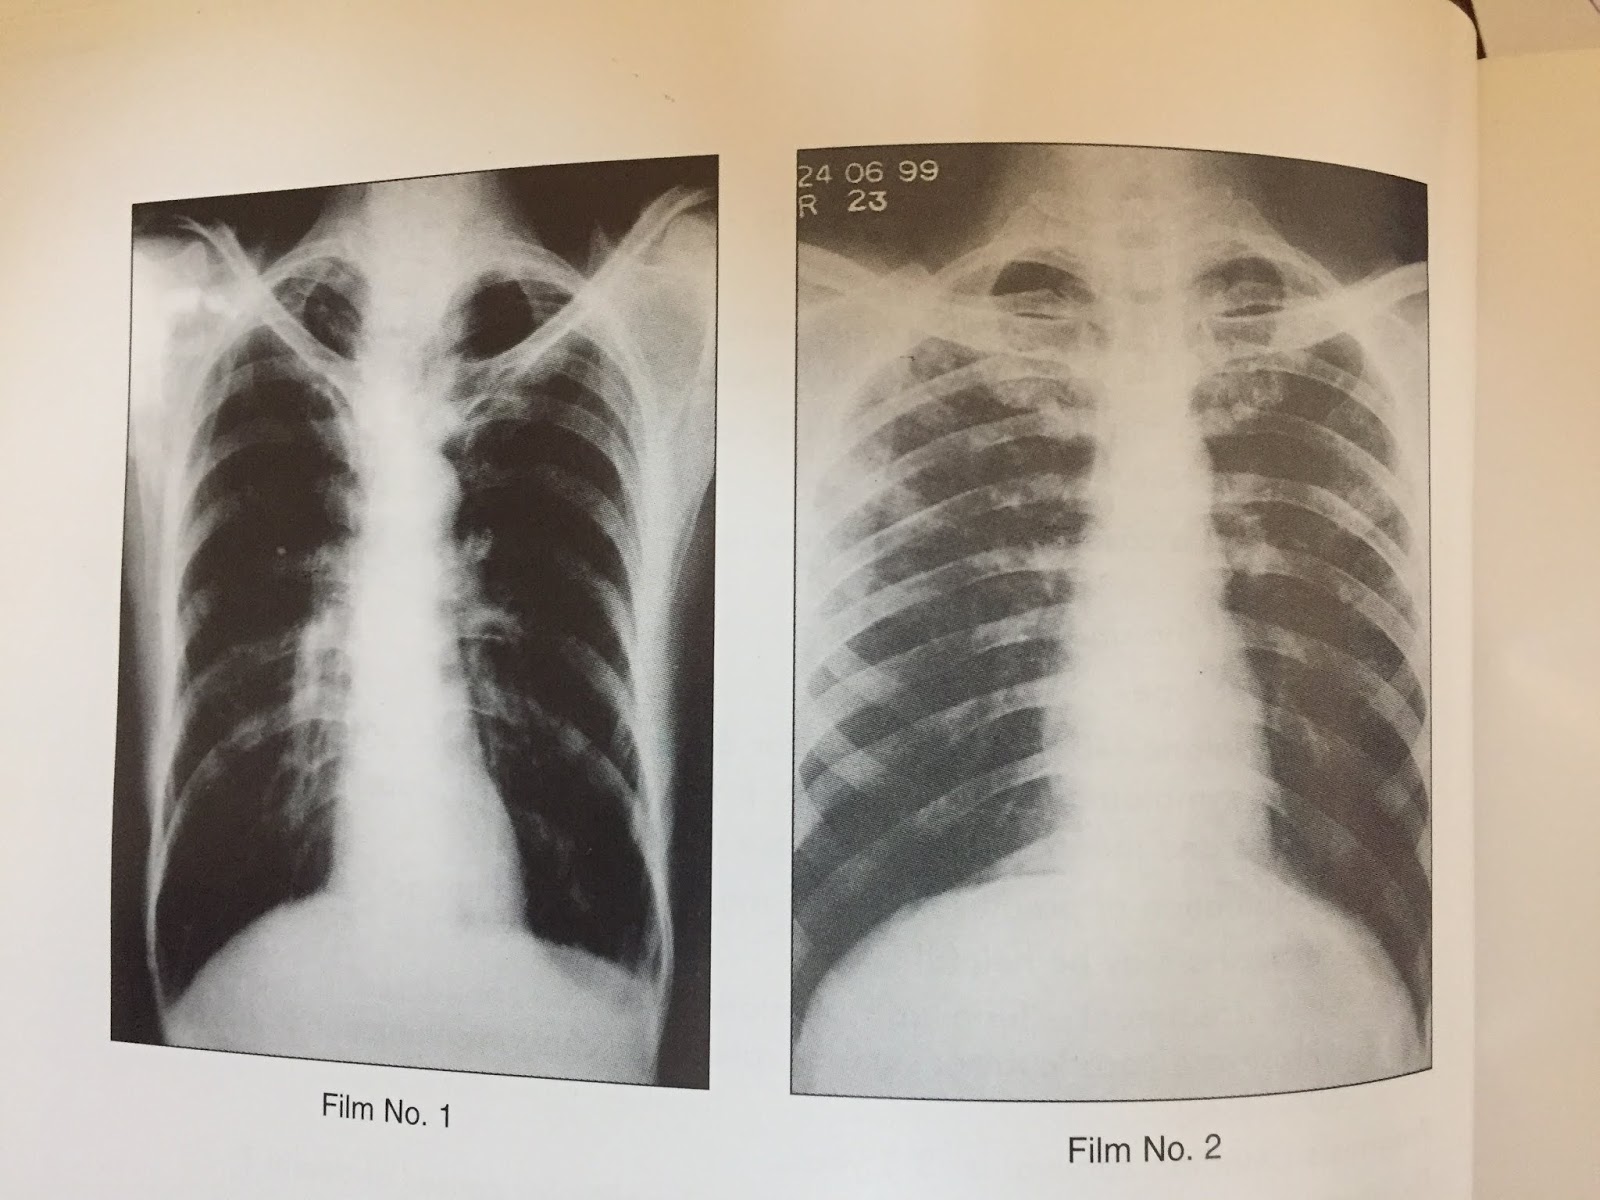

Emphysema X-Ray . In people with emphysema, the air sacs in the lungs (alveoli) are damaged. Over time, the inner walls of the air sacs weaken and rupture — creating larger air spaces instead of many small ones. the term ‘emphysema’ is generally used in a morphological sense, and therefore imaging modalities have an important role in. Conventional chest radiography is generally the first imaging procedure performed in patients with respiratory. emphysema is a lung condition that causes shortness of breath. emphysema manifests as lung hyperinflation with flattened hemidiaphragms, a small heart, and possible bullous changes.